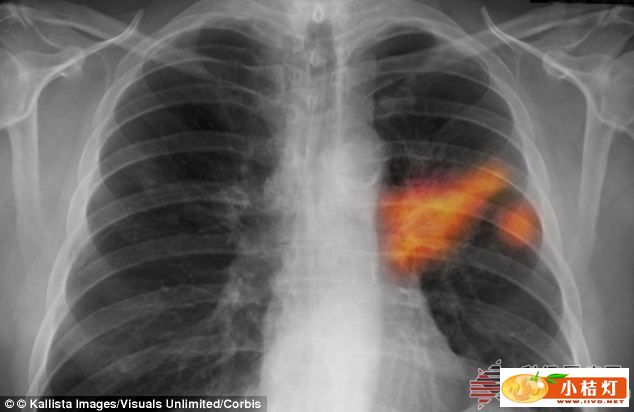

肺癌的死亡率要高于结肠癌、乳腺癌和胰腺癌等,这是因为肺癌常常不易早期发现,确诊时很多已经是晚期。

新式电子“鼻子”能早期诊断肺癌